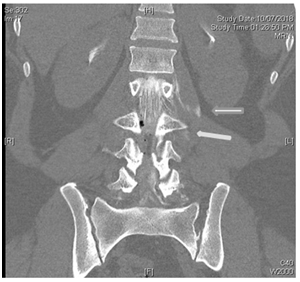

Under the suspicion of intracranial hypotensive headache caused by acute CSF leakage, a CT myelogram was performed Figure 3 the needle was set at L3/4 under radiographic control, contrast was repeatedly injected and x-ray images of lower and upper spine performed. After filling up to the cervical level of the epidural space, the patient’s whole spine was imaged with CT and extravasation was noted Figures 4 & 5.

Figure 4 Enlarged area CT spine with Contrast extravasation.